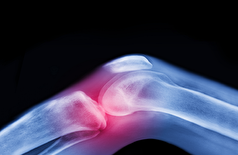

موثرترین درمان برای درد مفاصل قبل از متوسل شدن به داروها و جراحی

به گزارش مجله خبری نگار، اما واقعیت پزشکی نشان میدهد که این سرنوشت اجتنابناپذیر نیست. آرتروز - شایعترین بیماری مفصلی در جهان - را میتوان با روشهای غیر دارویی بسیار مؤثر پیشگیری و درمان کرد.

کارشناسان معتقدند که بهترین درمان برای آرتروز در جعبههای قرص یا اتاقهای عمل یافت نمیشود، بلکه در حرکت و ورزش منظم است. با این حال، مطالعات نشان میدهد که تعداد کمی از بیماران راهنمایی مناسبی در مورد نحوه استفاده از این درمان مؤثر دریافت میکنند.

تحقیقات انجام شده در سیستمهای مراقبتهای بهداشتی در ایرلند، انگلستان، نروژ و ایالات متحده، الگوی نگرانکنندهای را نشان میدهد: کمتر از نیمی از افراد مبتلا به آرتروز توسط پزشکان مراقبتهای اولیه خود برای فیزیوتراپی یا ورزش ارجاع داده میشوند. در همین حال، بیش از ۶۰٪ از این بیماران درمانهایی دریافت میکنند که با دستورالعملهای پزشکی مطابقت ندارد، در حالی که تقریباً ۴۰٪ قبل از امتحان کردن گزینههای غیرجراحی، برای جراحی ارجاع داده میشوند.